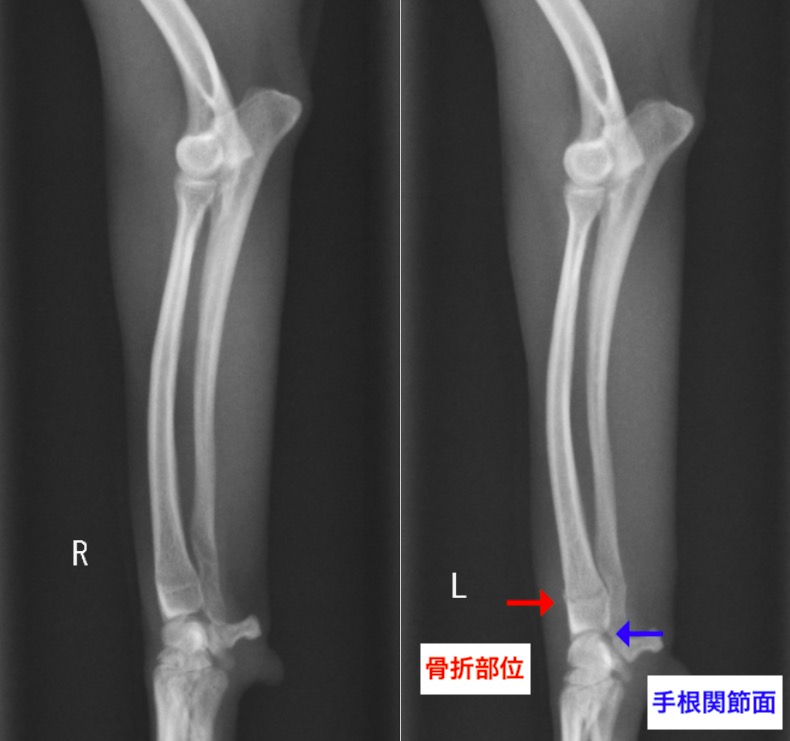

今回ご紹介する症例は橈尺骨骨折の中でも手首の関節に近い部分が折れてしまったチワワさんでした。

関節面から骨折線までは6mm程度しかありませんでした。

左:術後 / 右:術前